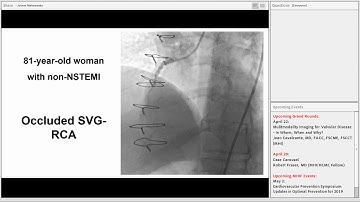

Case 31: Manual of CTO Interventions - PCI of two CTOs with hemodynamic support